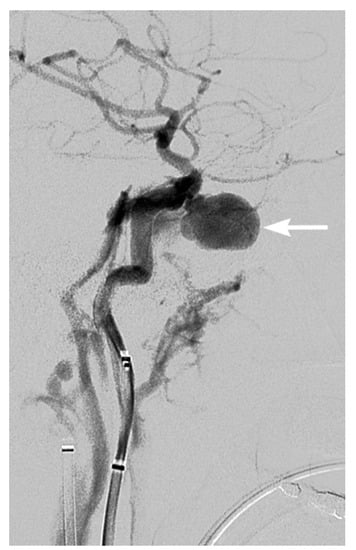

3. Imaging Findings of Arterial Injury

4. Screening for Blunt Cerebrovascular Injury